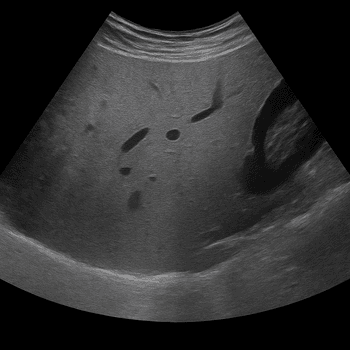

Undersökningen ger högupplösta bilder av leverns struktur, blodflöde och gallvägar och används både vid misstanke om sjukdom och för uppföljning av tidigare fynd. MR är den mest känsliga metoden för att skilja godartade förändringar från elakartade och kan ofta ge mer information än ultraljud eller datortomografi.

En MR-undersökning av levern tar vanligtvis 20–40 minuter och utförs i liggande position. Undersökningen är helt smärtfri och använder ingen röntgenstrålning. I vissa fall ges kontrastmedel för att förbättra bildkvaliteten och bedöma blodflödet i levern.